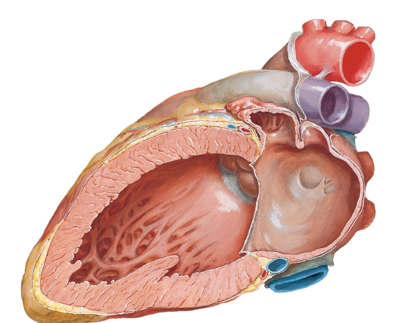

A

View of the left atrium and ventricle (sectioned with mitral valve cut away)

Fossa avoalis pictured in left atrium